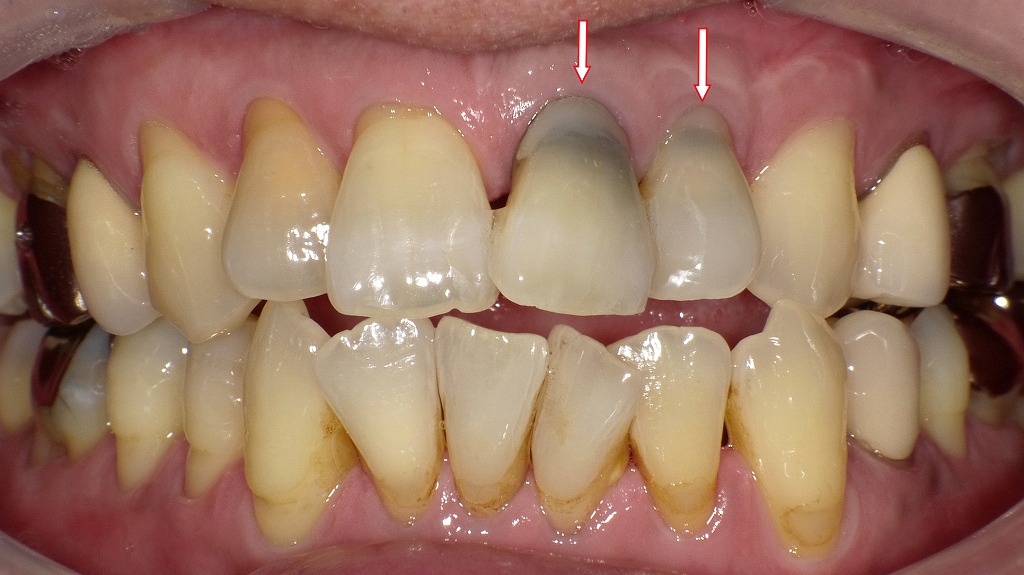

神経の死んだ歯の変色

この画像は、上顎前歯部の歯の変色の状態を示しています。赤い矢印で示された歯(上の前歯2本)は、いずれも神経が死んでいる(失活歯)ために黒ずんで見えています。以下に詳しく解説します。

🦷 見られる症状の特徴

- 歯の変色(灰色〜黒っぽい色)

- 神経(歯髄)が死んでしまうと、歯の内部の血液やタンパク質が分解され、歯の内側から変色します。

- このような変色は、打撲・虫歯・過去の根管治療などが原因で起こります。

- 歯肉(歯ぐき)の黒ずみ

- 矢印の部分で、歯肉がやや黒っぽく見えるのは、歯の中の古い根管充填材(ガッタパーチャなど)が透けている可能性があります。

- いわゆる「メタルタトゥー」や「根尖部の変色」によるものです。

- 歯列・歯石の沈着

- 下の前歯や臼歯部に歯石やステインの沈着も見られ、歯肉炎や歯周病の兆候があると考えられます。

🩺 原因

- 外傷(転倒・打撲など)による歯髄壊死

- 深い虫歯が神経に達して壊死した

- 過去に根管治療を受けたが、内部の変色が進行した

💡 治療法

- 根管治療(根の中の清掃・消毒・充填)

- 既に失活している場合は、感染を防ぐために根管治療を行います。

- 再治療が必要なこともあります。

- 歯のホワイトニング(ウォーキングブリーチ)

- 神経がない歯の内部から漂白する方法で、内部漂白とも呼ばれます。

- セラミッククラウン・ラミネートベニア

- 変色が強い場合や審美的に改善したい場合は、被せ物で自然な色に回復させることができます。